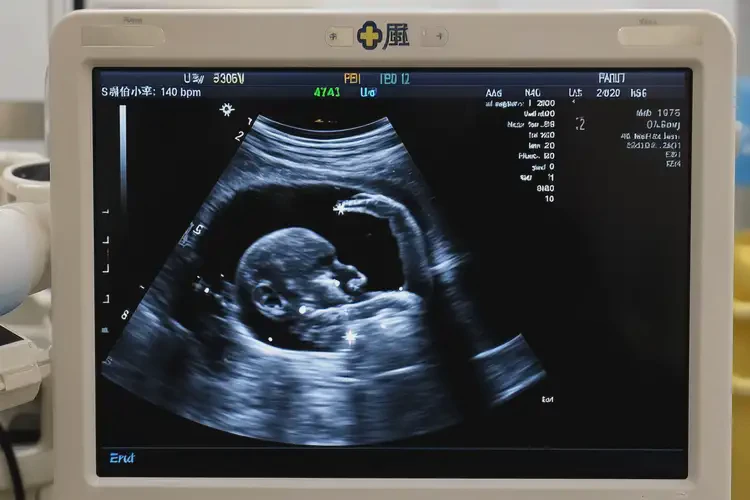

孕30周6天胎心率70多有危險嗎(圖1)